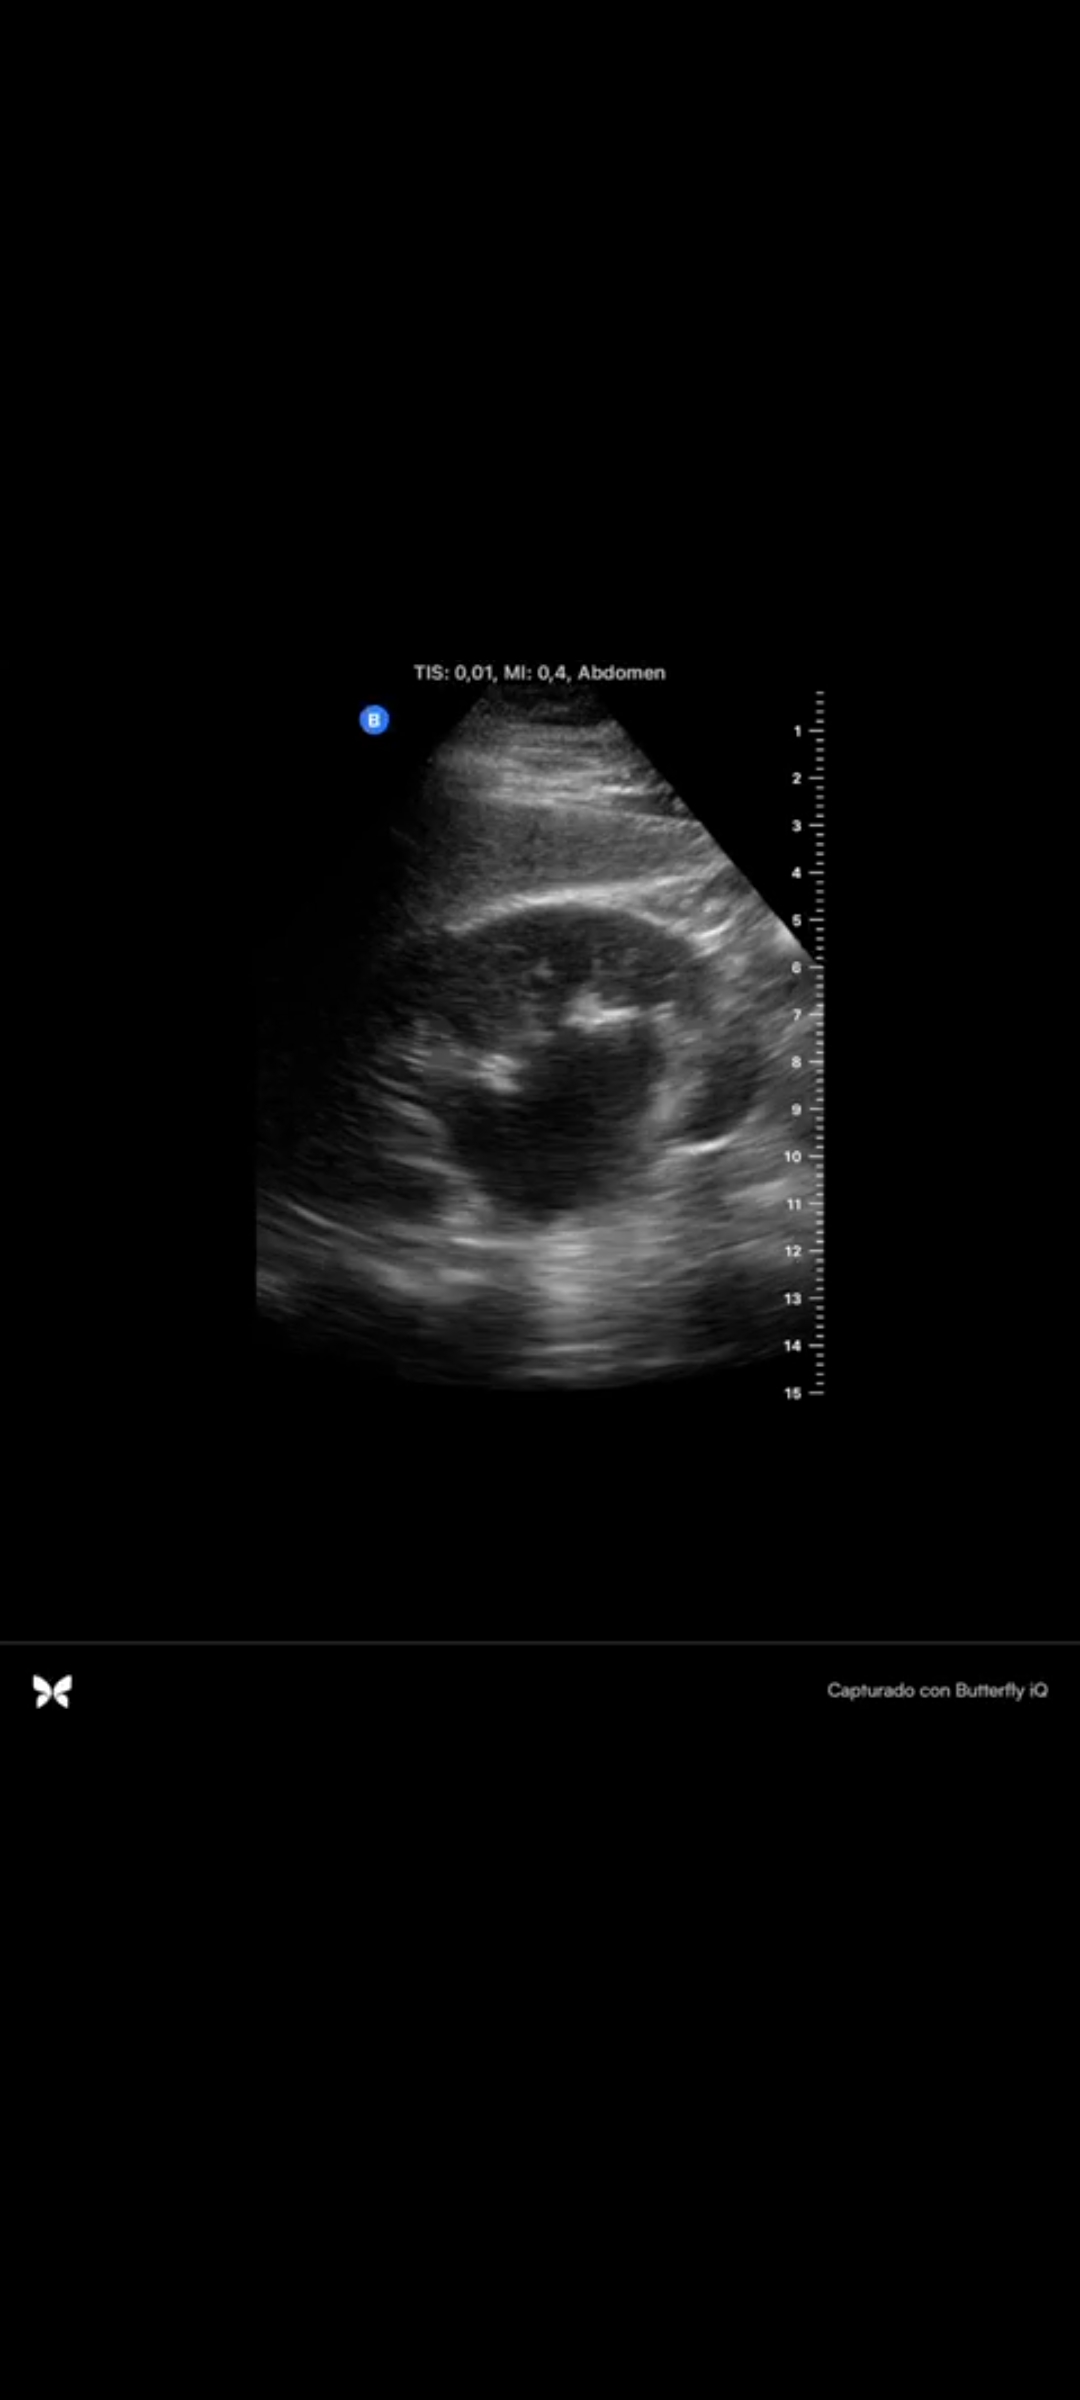

En la ecografía se objetiva hidronefrosis moderada renal derecha sin conseguir visualizarse cálculo renal.

Hidronefrosis en paciente con cólico renal.

El cólico renal es un motivo de consulta relativamente frecuente en urgencias de atención primaria, siendo las litiasis renales la causa más frecuente de los mismos. Ante un paciente con sospecha de cólico renal debemos tener en cuenta las posibles complicaciones, como son la obstrucción con aparición de hidronefrosis y empeoramiento de la función renal asociada.